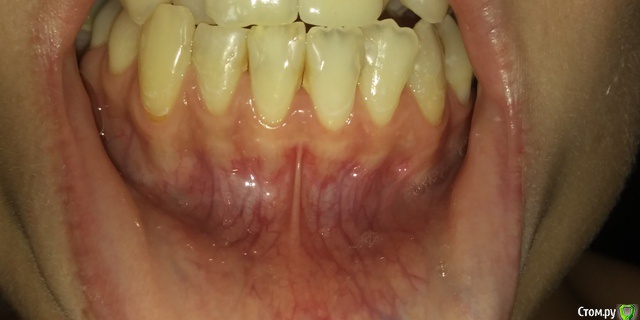

Есть рецессии на нижних зубах и на верхнем клыке слева и резорбция. Ортодонты говорят, что это последствия неправильного прикуса, травмирующего смыкания и с брекетами все стабилизируется, но из-за движения зубов может и усугубиться, как повезет. Вестибулопластику никто не предлагал, а один вообще сказал, что в моем случае она бесполезна. У хирурга-парадонтолога другое мнение: нужно сделать сначала операцию на нижних зубах (углубить преддверие, устранить тяжи и положить какой-то там замещающий материал), а потом поставить брекеты, иначе без операции брекеты спровоцируют еще большее оголение и рецессии станут просто огромными.  А после брекетов уже закрывать, если нужно, рецессии.  Прошу поделиться вашим мнением? В чем причина рецессий и резорбции? Поможет ли в моем случае вестибулопластика?